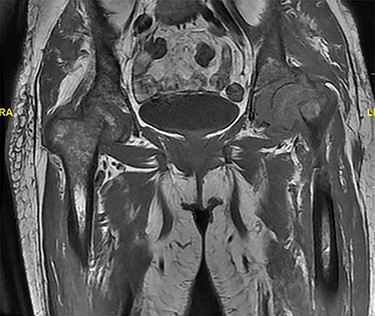

MRI showing displaced fracture noted at the left femoral neck and subcapital right femoral neck fracture with minimal reactive changes.

A 60-year-old lady, community walker with no assistance of a cane or walker, known to have PMF on ruxolitinib. She was diagnosed with PMF in a different hospital 4 months prior to presentation (Fig. 1). She presented to our clinic with 8-month history of progressive left hip pain and was not able to bear weight since the initial episode of pain without the use of analgesia. The pain was relieved with analgesics and intra-articular injections previously, which stopped showing benefits prior to presenting to our clinic. The patient did not report any history of trauma or falling down, no fever or loss of appetite. Range of motion of the hip was severely restricted due to pain. Greater trochanter tenderness was noted on examination. Initial x-rays were ordered (Fig. 2) and revealed a possible left neck of femur fracture, which prompted us to order an MRI that showed a displaced neck of femur fracture in the left hip and a non-displaced neck of femur fracture of the right hip (Fig. 3). Surgical intervention for the left neck of femur fracture was offered to the patient, while the right neck of femur fracture was asymptomatic and conservative treatment was preferred. The patient favored surgery and requested to be done as soon as possible. She was admitted from the clinic to the ward for preoperative clearance and planning.